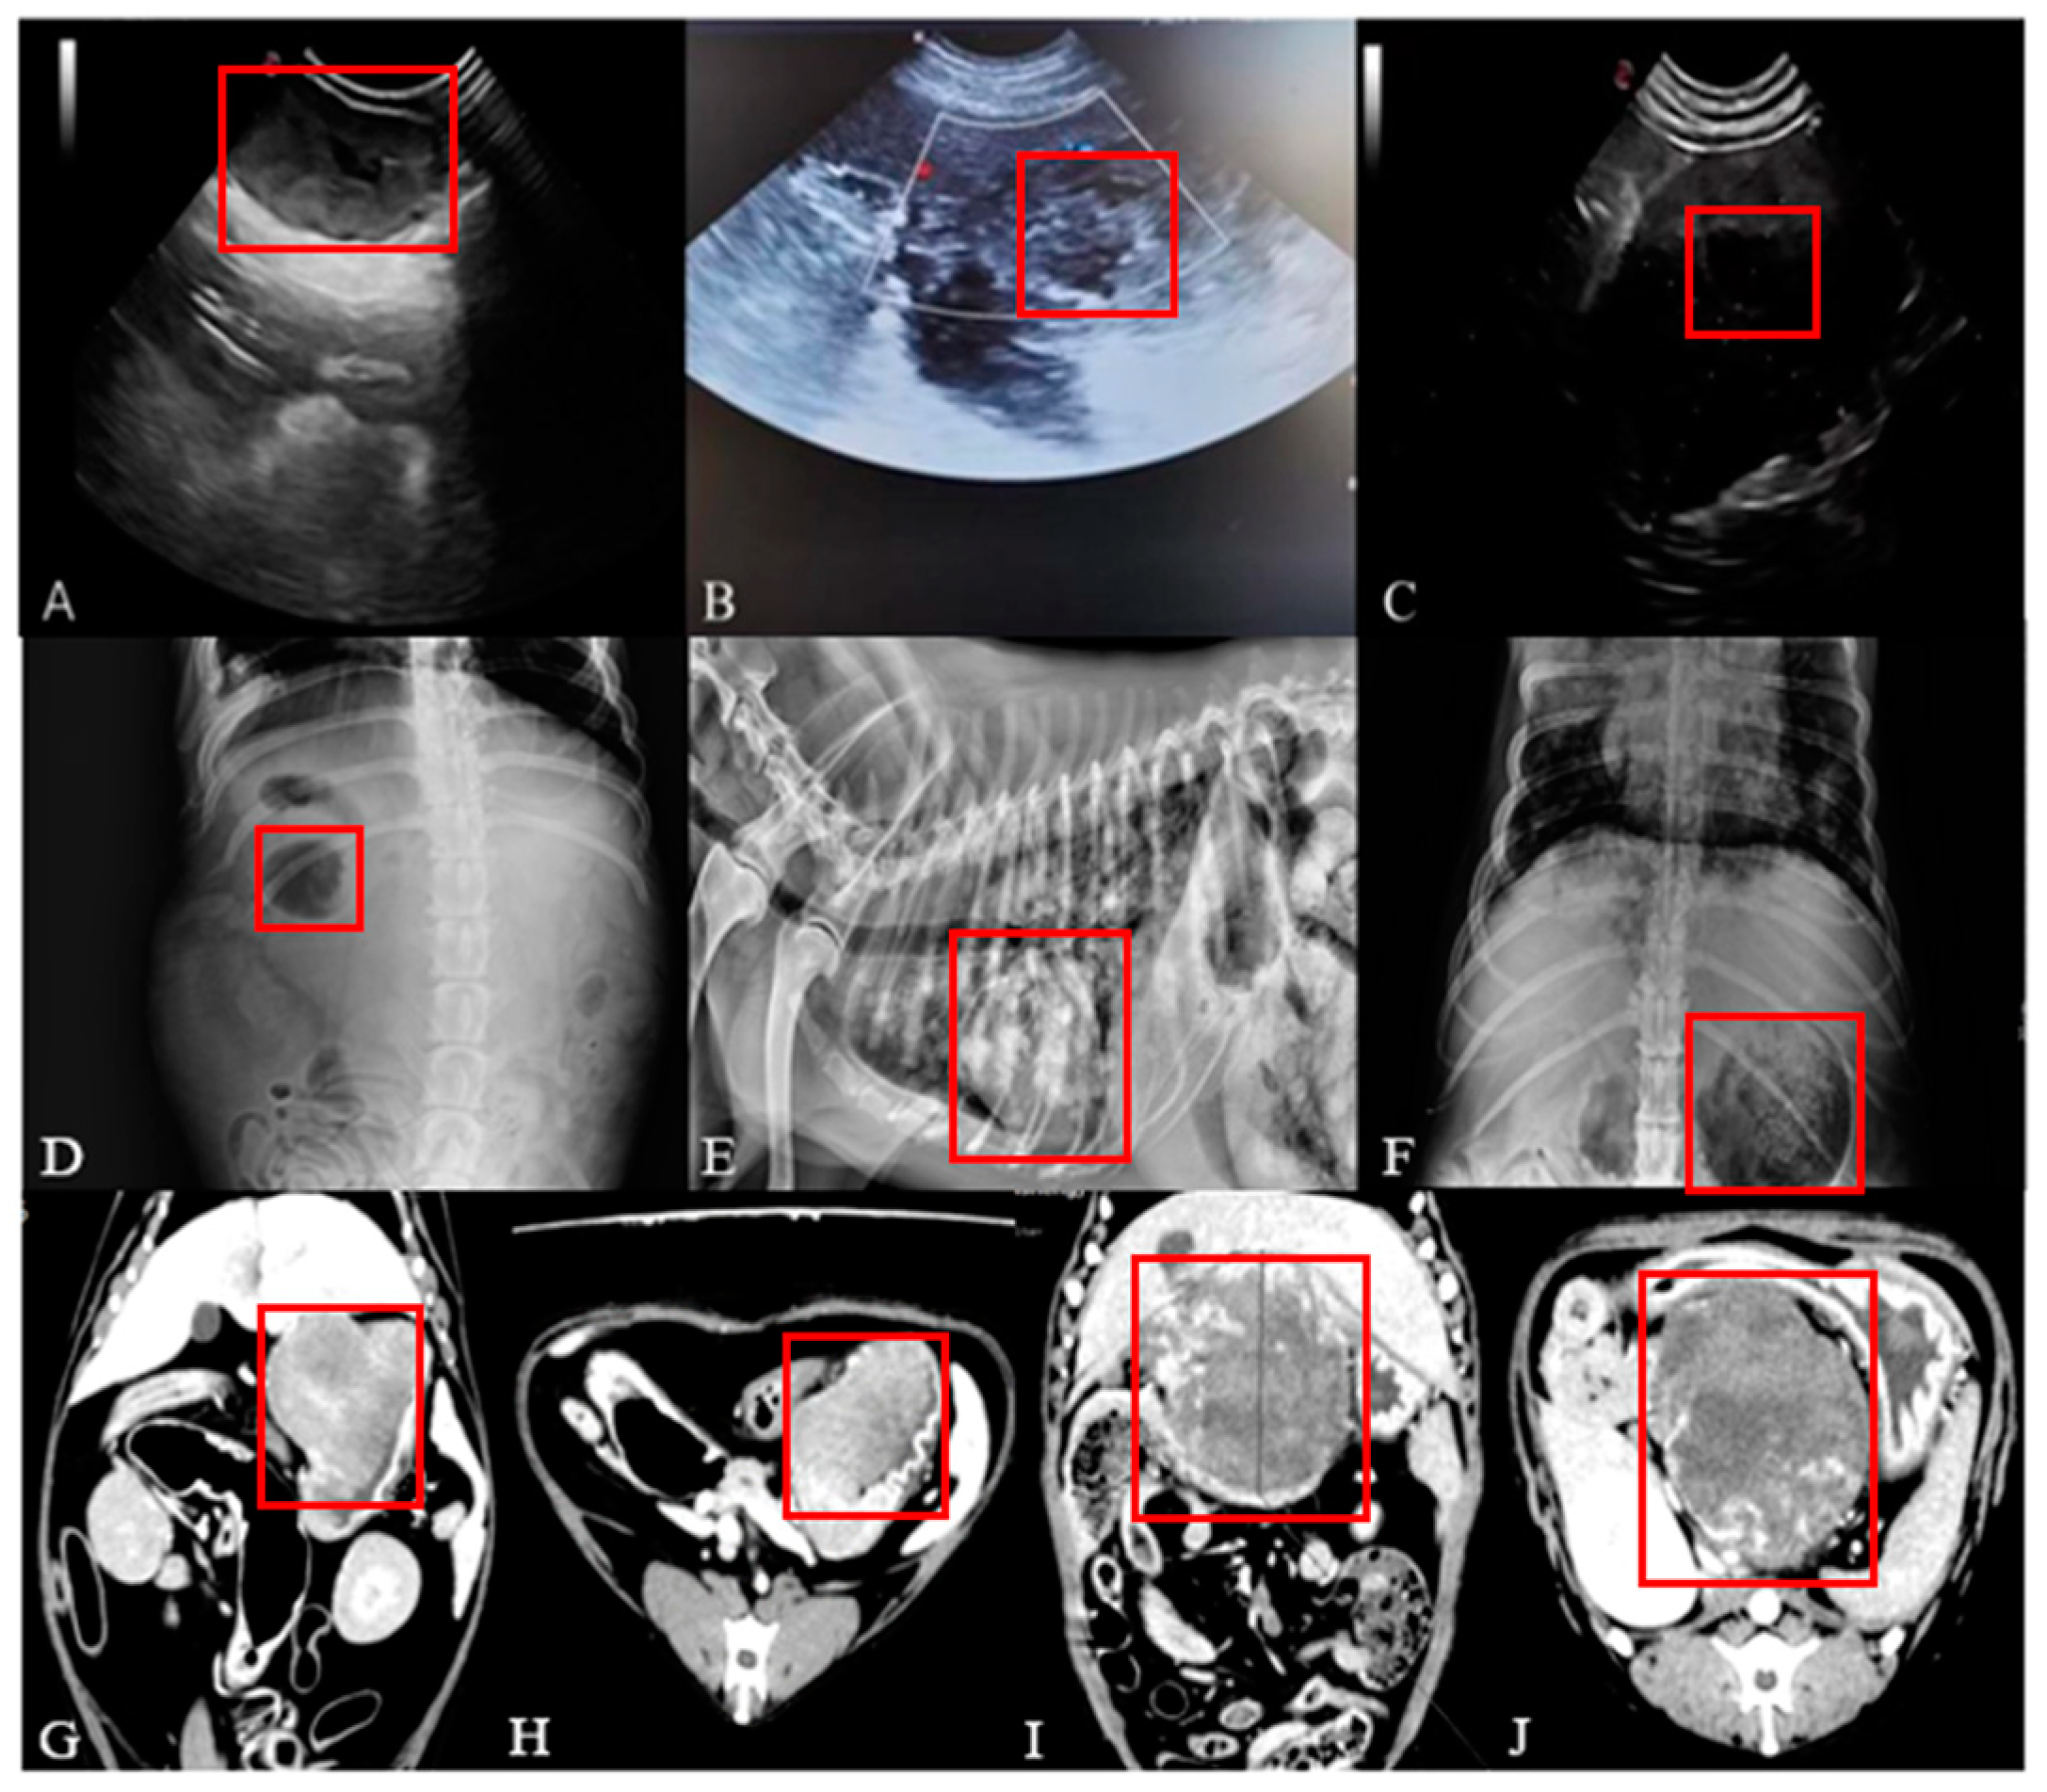

Figure 2A–J include the tumor morphology by ultrasound, X-ray, and CT imaging and the tumours can be seen in the red boxes.

Figure 2.

Canine tumour imaging results.

The mass is heterogeneous in texture and may be malignant if it appears as a hyperdense image (Figure 2A–C).

The tumour site in the affected dogs showed either higher or lower-density images than the surrounding tissues (Figure 2D–F).

The results of the CT examination showed that the three-dimensional images are able to better present the size, morphology and relationship of the tumour to the surrounding tissues (Figure 2G–J).